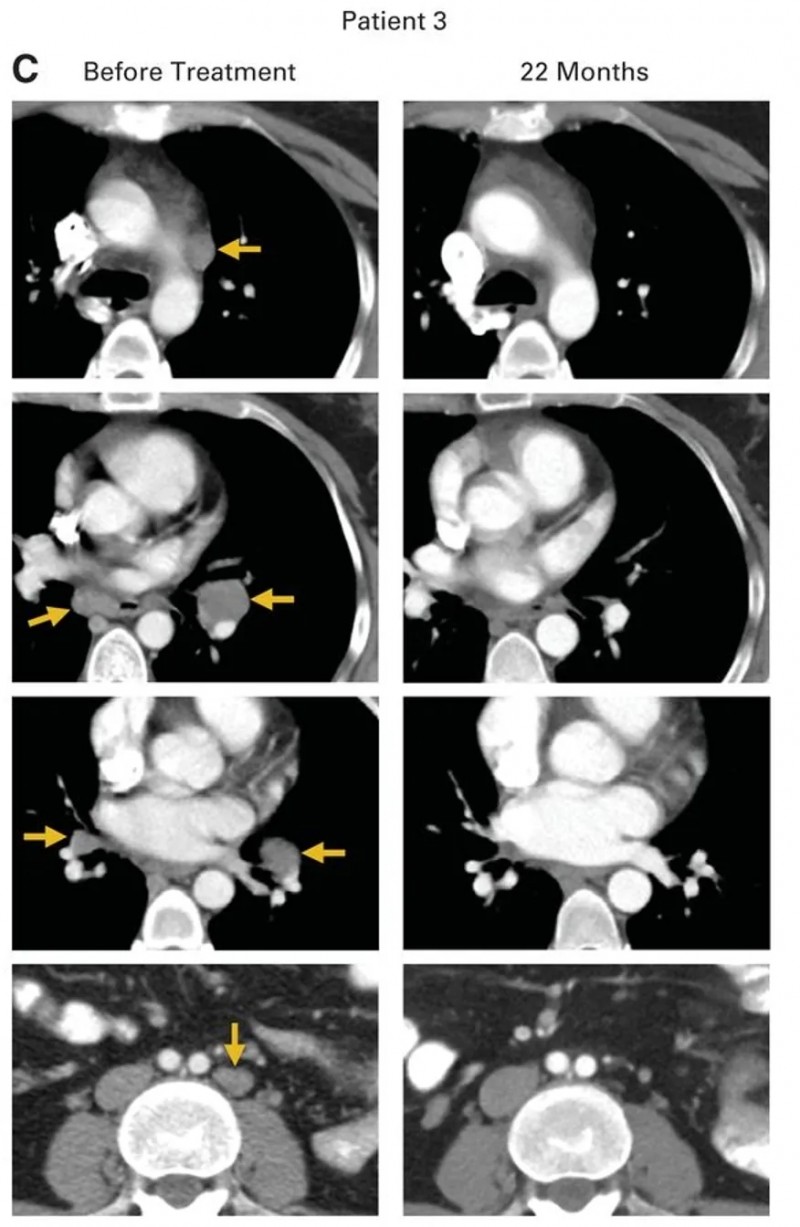

患者3是一位转移性鳞状细胞癌患者,此前接受过诱导化疗、吉西他滨联合顺铂放化疗,以及拓扑替康和紫杉醇治疗,病情仍进展并转移至腹主动脉旁、双侧肺门、隆突下和左髂淋巴结等多个部位(详见下图C,金色箭头所示)。在接受HPV-TIL治疗后,所有病灶完全消退(详见下图C),且治疗后22个月未见疾病复发。

▲图源“JCO”,版权归原作者所有,如无意中侵犯了知识产权,请联系我们删除